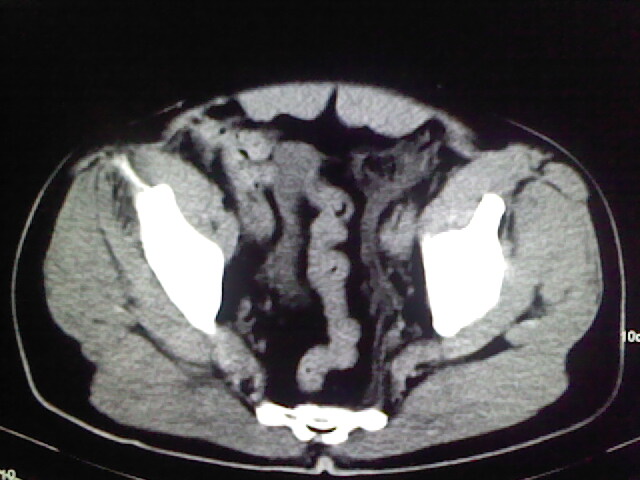

以下是引用zsl6918在2009-2-7 7:29:00的发言:[br]请提供介入的方式方法,肾及输尿管改变考虑与介入损伤有关,漏了,尿液外渗。

以下是引用余辉在2009-2-7 8:27:00的发言:[br]可能是硬化剂烧穿囊壁进入肾盂输尿管了,尿漏。不除外介入或碎石术后合并感染[br]患者术后怀疑结石,接着就碎石了?就怀疑没有确诊吗?碎石用的什么方法?气压弹道还是体外超声?如果这样的话责任人都难找

以下是引用随光逐影在2009-2-7 8:46:00的发言:[br]支持3楼意见。[br]另:不排除左肾及肾周感染可能。